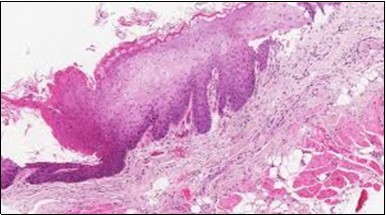

Figure 1.HCL: hairy cells infiltrating designated spaces(17).

HCL: hairy cells infiltrating             designated spaces(17).